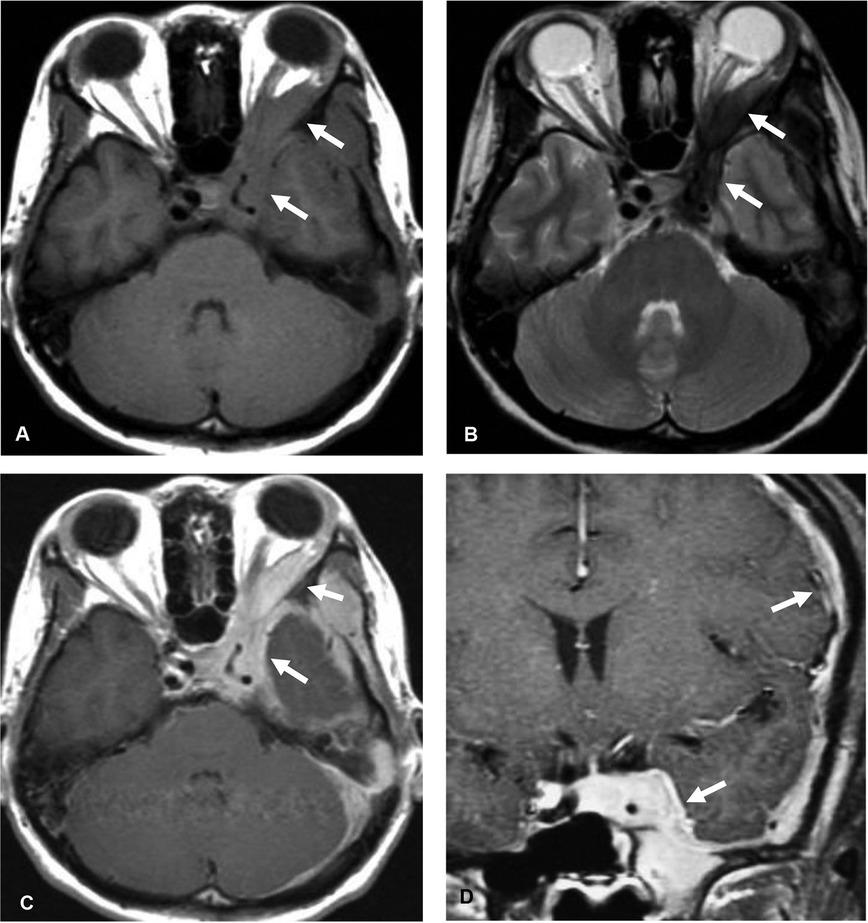

Figure 2